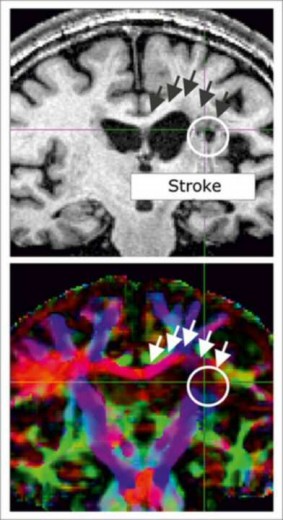

Para comprobar la conexión estructural entre las áreas cerebrales, los investigadores usaron resonancia magnética del tipo dMRI. En comparación con el grupo de control, los que habían padecido un derrame tuvieron valores inferiores de difusión en la región del cuerpo calloso. Esto indica que el derrame dañó esa conexión de comunicaciones entre ambos hemisferios.![[Img #6034]](upload/img/periodico/img_6034.jpg)

Por tanto, además de la muerte celular en el área principal del derrame, los daños ocasionados a una estructura conectiva distante desempeñan un papel crucial en la incapacidad que experimentan estos pacientes para recuperar completamente sus capacidades motoras originales.